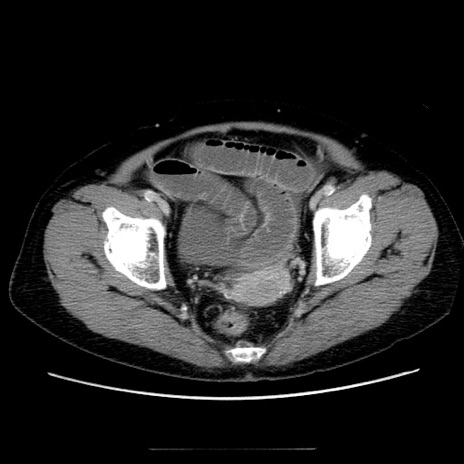

症例5(横断像)

【症例】70歳代女性

【主訴】お腹が張る

【現病歴】1週間くらい前から腹部膨満の自覚あり。昨日夜から増悪したため、本日救急外来受診。

【身体所見】意識清明、BT 36.5℃、BP 165/106mmHg、HR 80bpm、SpO2 98%、腹部:膨満、軟、自発痛・圧痛なし、触診にて不快感あり、腸蠕動音:減弱

【データ】WBC 12600、CRP 1.04